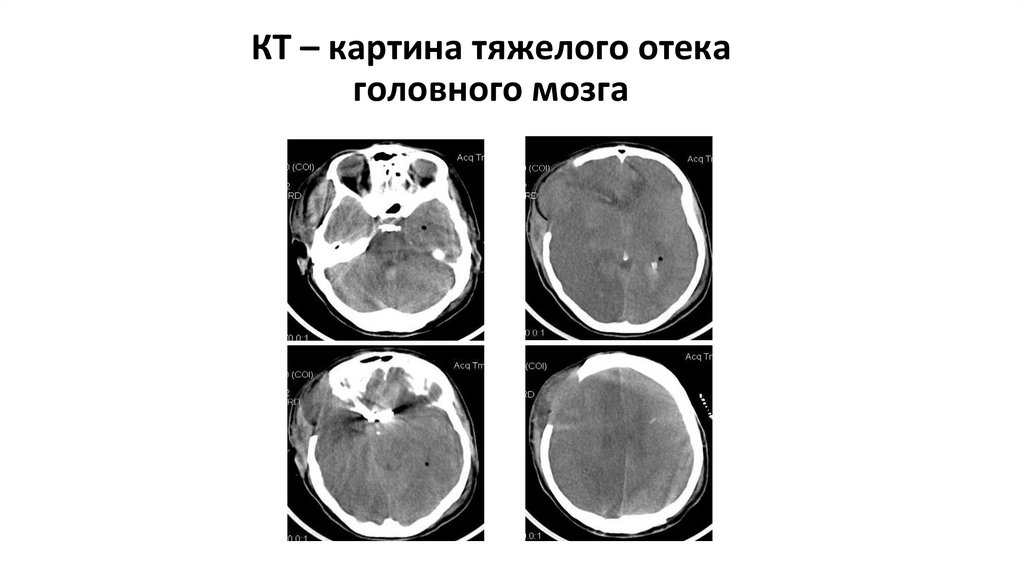

КТ – картина тяжелого отека головного мозга

60. КТ – картина тяжелого отека головного мозга